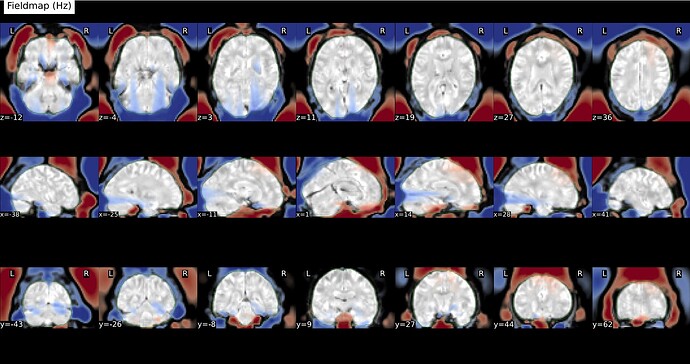

Feed FMRIPREP with the native BOLD image and give in the

fmap/folder: the fieldmap in Hz and undistorded magnitude image generated by topup run by SYNB0-DISCO. In that case FMRIPREP would use the Direct B0 mapping method for SDC. That could work! To be tested.

EDIT: for the last method, SynBOLD-DISCO does not output a fieldmap from topup , one would need to run topup again with the output of SynBOLD-DISCO with the option --fout and giving in acqparams.txt the correct value for the total readout time of the bold serie. To be tested, I am not sure it will work.